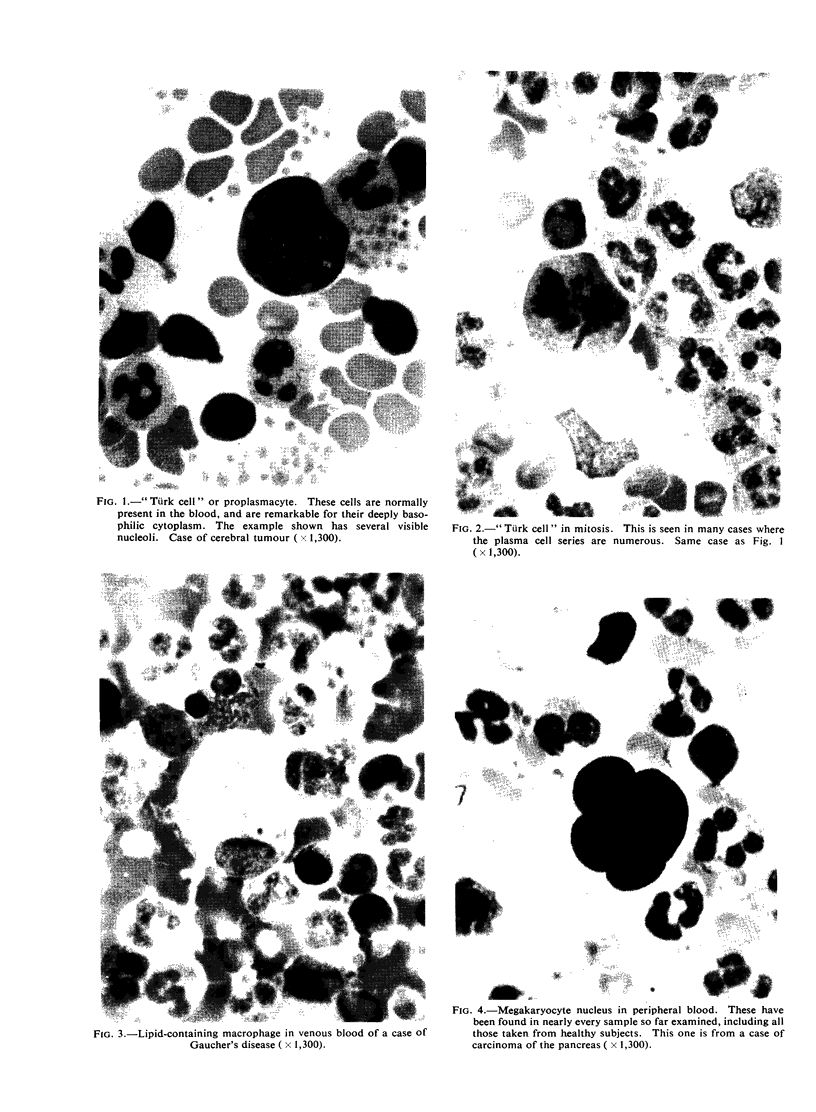

White-cell concentrates were made by a dextran sedimentation technique from the blood of 140 cases of malignant disease and 60 controls. The slides were searched for tumour cells and for other unusual cells with which they might be confused. Several million white cells were scanned in the slides from each case.

Acceptable tumour cells were identified in the blood of seven patients, none of whom survived for more than a few months. These cells are illustrated, as well as various other cell types which may have been confused with malignant cells in the past. It is concluded that the cytology of white cell concentrates should be further explored before statistics about the occurrence of circulating tumour cells are accepted.